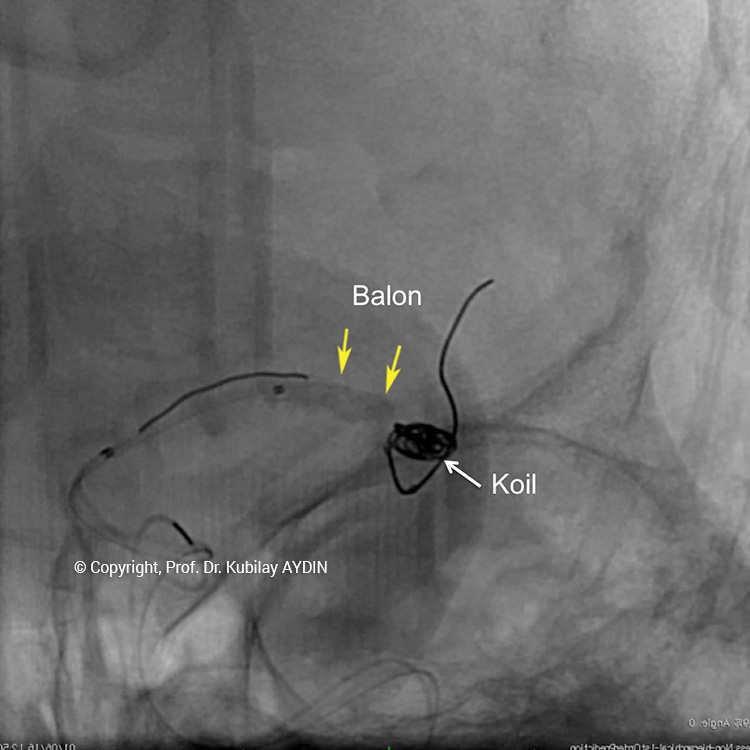

Geniş boyunlu anevrizmaların endovasküler tedavisinde kullanılan diğer bir yöntem "Balon-yardımlı koilleme" dir. Bu yöntemde anevrizma içine konulan koillerin damar içine sarkması, damar içinde çok kısa bir süre için şişirilen balon kateteri yardımıyla engellenir. Damar içinde şişik vaziyetki balon, anevrizma kesesi içine yerleştirilen koillerin damar içine sarkmasını önler. Koil, uygun şekilde yerleştirildikten sonra balon söndürülür. Bu işlem anevrizma tamamen dolduruluncaya kadar tekrarlanır.